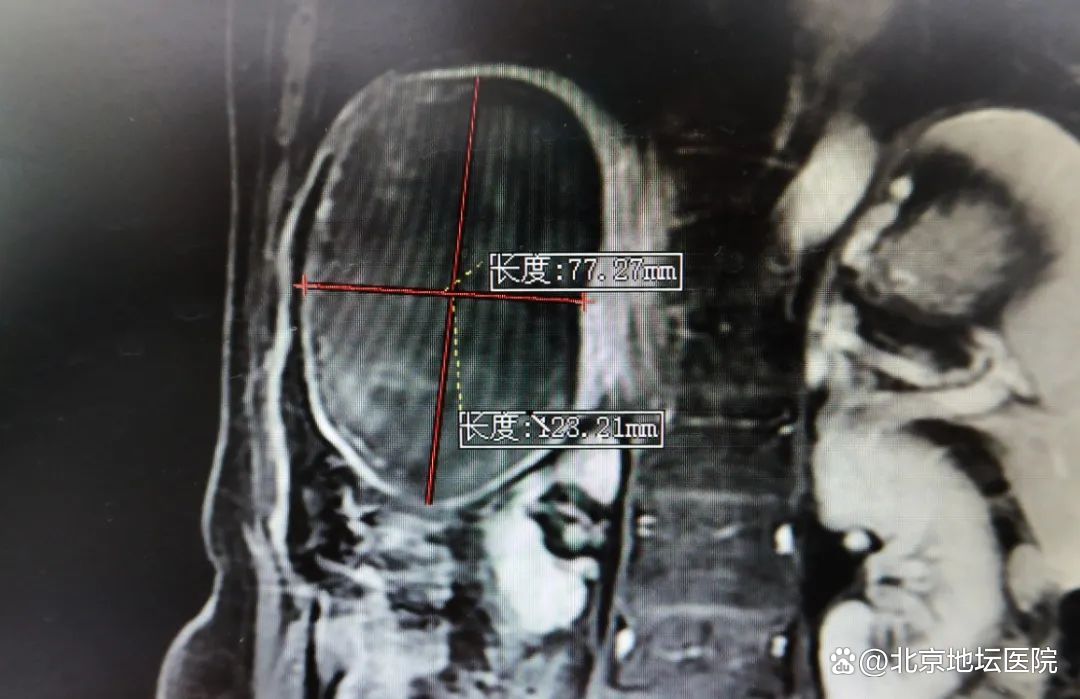

2010年3月,刘奶奶在地坛医院进行丙肝的抗病毒治疗,随后,在2012年复查中,确诊为肝癌中期。由于刘阿姨的身体对于靶向药物治疗不耐受,加上年纪较大,肿瘤介入科医生团队根据检查结果进行了充分地分析和讨论,决定采取介入治疗。在之后的一年半的时间里,刘阿姨进行了三次肝动脉化疗栓塞术。由于此后的复查中并未发现肿瘤的进展和复发,这让刘奶奶和她的家人放松了警惕,没有定期复查。刘奶奶自己也没有感觉到任何异常,而在2018年的检查中突然发现肝脏竟有两处新病灶,肿瘤已发展至最长处有12公分大小。